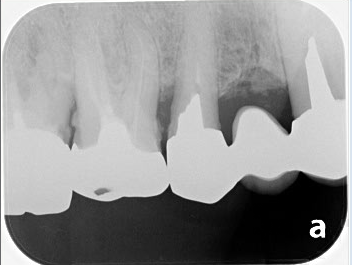

レントゲン上で左から2番目の歯の根管治療を行いました。

治療前は根の先に黒い像が確認できますが、治療後にはかなり縮小しているのが確認できました。